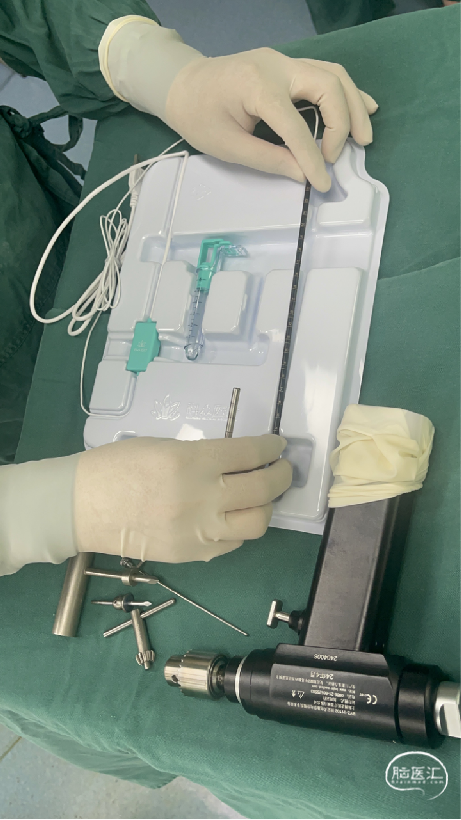

治疗:脑室穿刺,对侧脑血肿引流。

手术过程

扫码观看手术视频